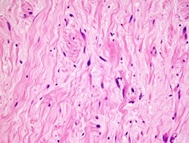

Contrast-enhanced computed tomography of the chest was requested to see the extent of the lesion on the chest wall. On the thorax CT was seen lesion in size 51x28x25cm in the axial axis at anterolateral 5th intercostal space in extrapulmonary localization. Density of protruding noduler lesion was average 10 HU (Figure 1).

Figure 1: Tomography image of the patient (axial).